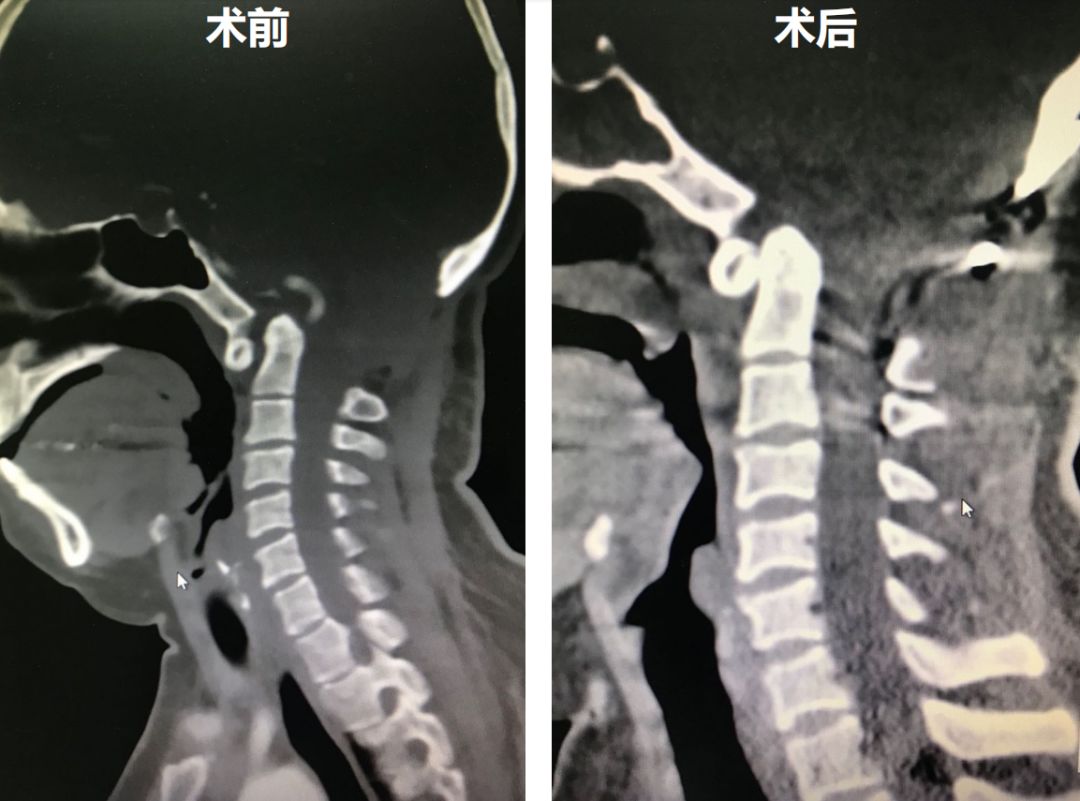

术后患者颅底凹陷得到改善,同时斜坡颈椎角也有明显恢复,右侧绞索的侧方关节得到复位。

对比术前和术后的矢状位CT,可见齿状突内陷明显改善。

术后复查MRI,提示脊髓空洞明显改善。